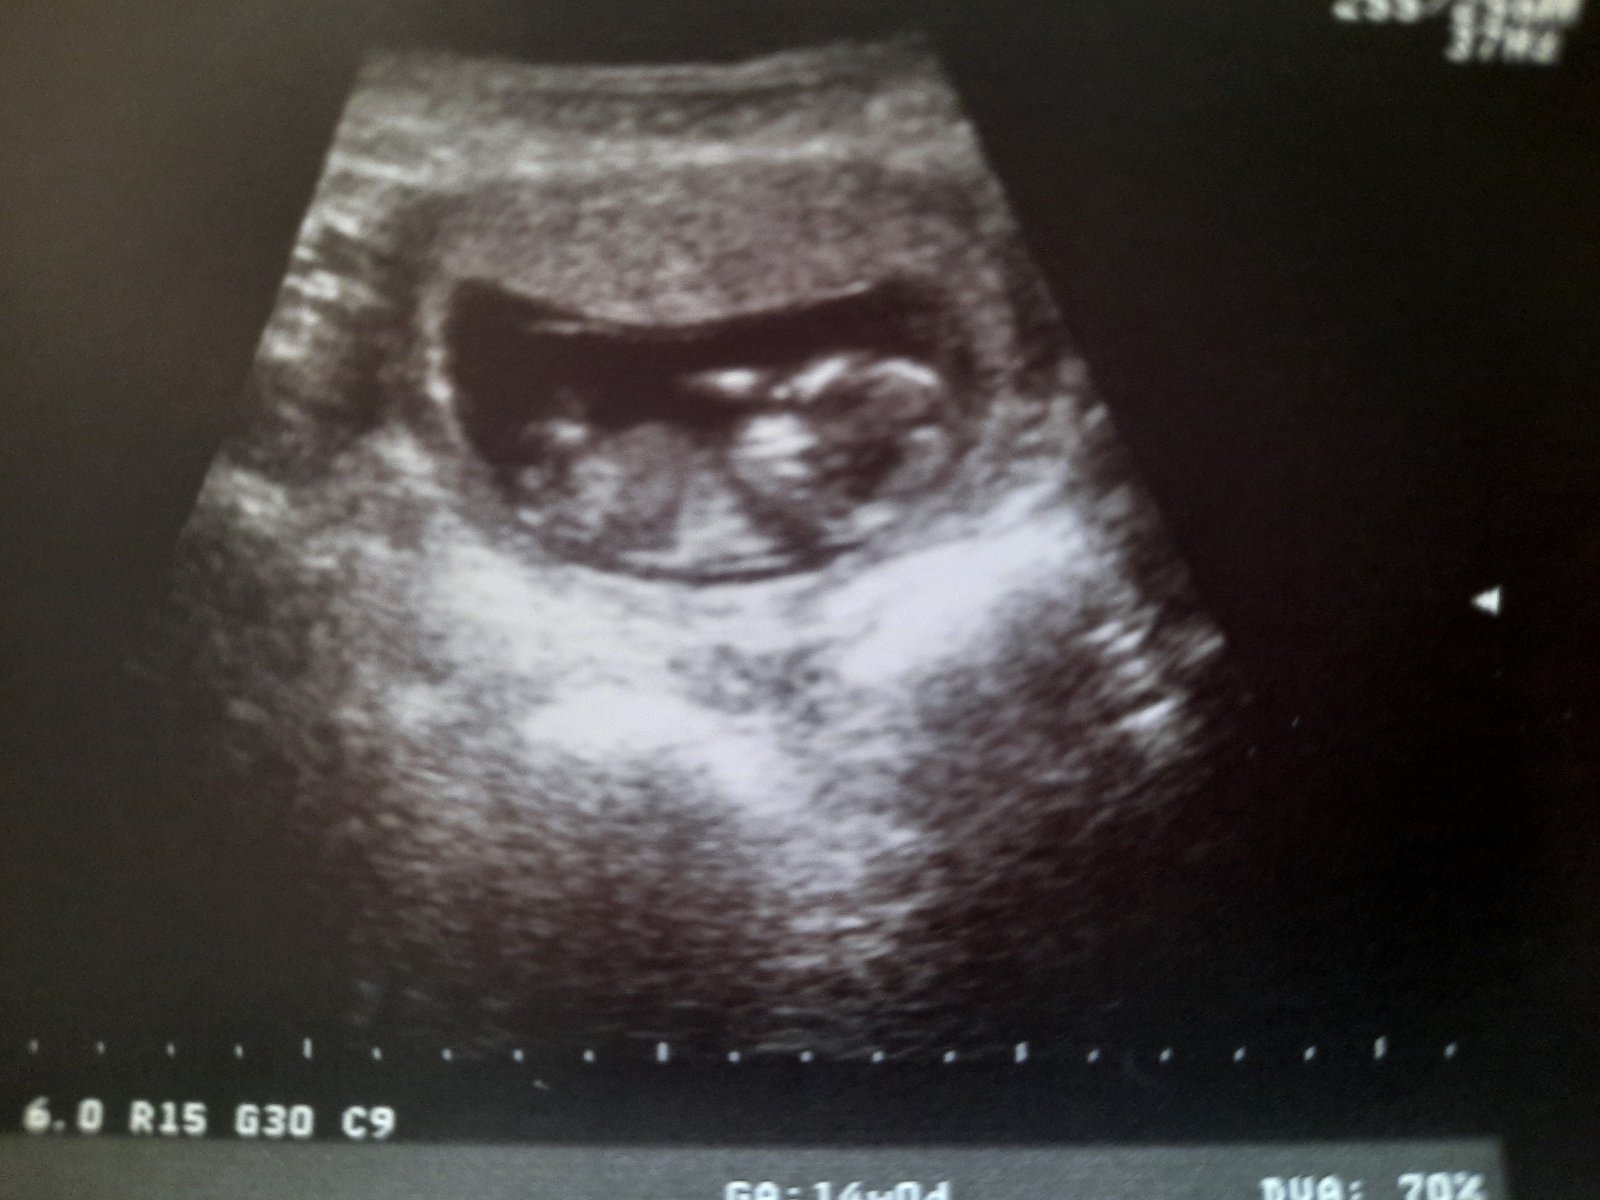

@juliemichal holkaaaa ♥️

@hawah ano na 80% po čtyřech chlapečcích ❤ ❤

Holka 🎉🎉🎉

@juliemichal no fakt, že jo. Ta druhá fotka je jasná. Hurá 🎉🎉🎉netrpělivě jsem čekala a tobě to hrooozne moc preju 🤗😘🌹🌷🌼

@sebinka123 holky, tak jste se trefily, čekáme holčičku 🙂